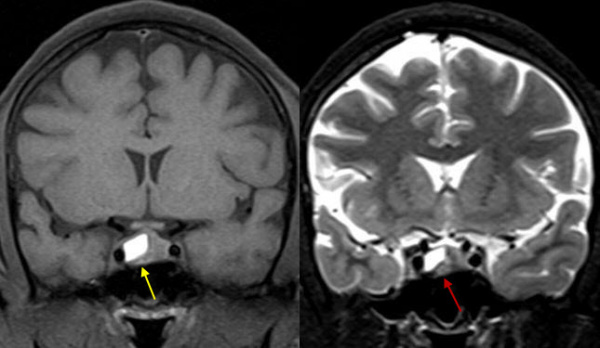

МРТ головного мозга (8 октября 2015 г.): обычные размер и конфигурация боковых желудочков мозга; хи-азмальная область без особенностей; размер гипофиза 1,6 х 1,5 х 1,3 см, структура его неоднородная за счет наличия в аденогипофизе участка измененного сигнала размером 1,0 х 0,9 х 0,8 см — аденома с признаками кровоизлияния; субарахноидальное пространство не изменено; срединные структуры не смещены. Изменений очагового и диффузного характера в веществе мозга не выявлено. Заключение: МРТ-признаки аденомы гипофиза с кровоизлиянием.

ного увеличения объема образования из-за скопления крови и резкого повышения давления не только в полости турецкого седла, но не были сдавлены хиазма и другие соседние структуры мозга. Дозу каберголина в дальнейшем следует корректировать в соответствии с показателем пролактинемии. Повторная МРТ гипофиза и контроль тропных гормонов проведены в феврале 2016 г.: на месте апоплексии формируется киста.